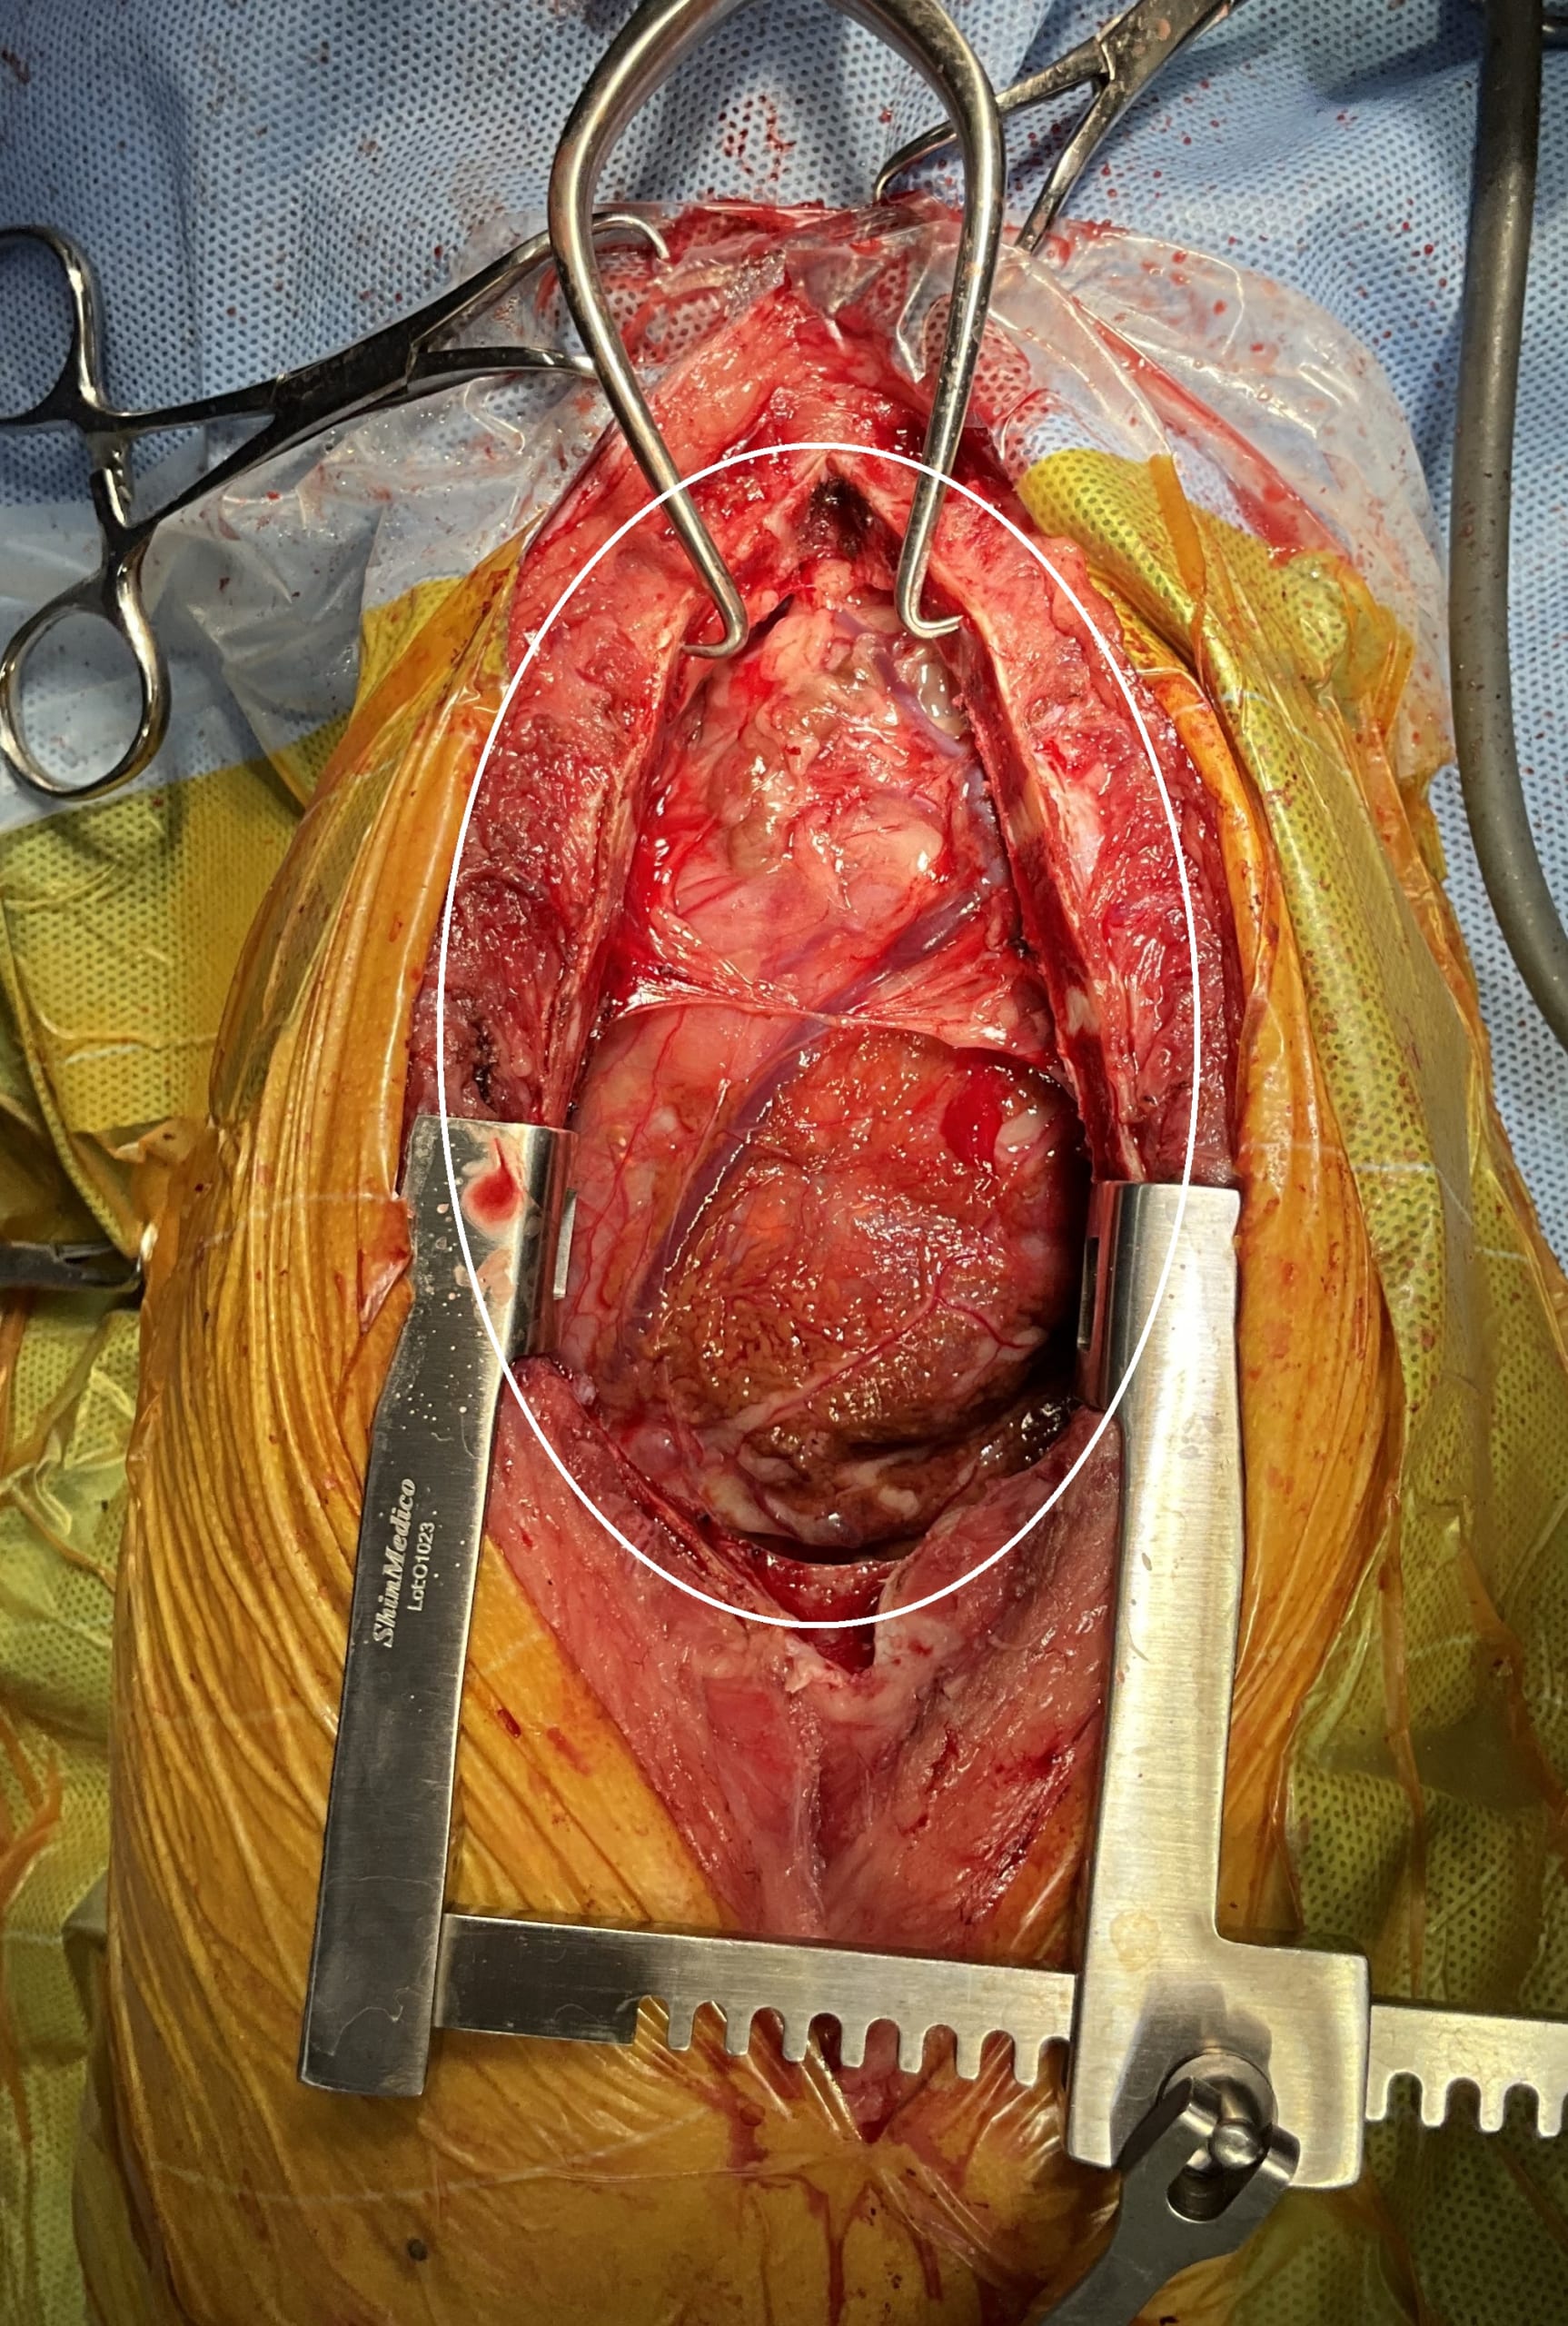

腫瘤摘出直後の胸腔内です。

腫瘤により肺が圧迫されていたため、摘出直後は肺が十分に拡張せず、胸腔内に空間が認められました。

しばらくすると、圧迫されていた肺(黒矢印)が徐々に膨らみ、呼吸の改善が期待できる状態となりました。